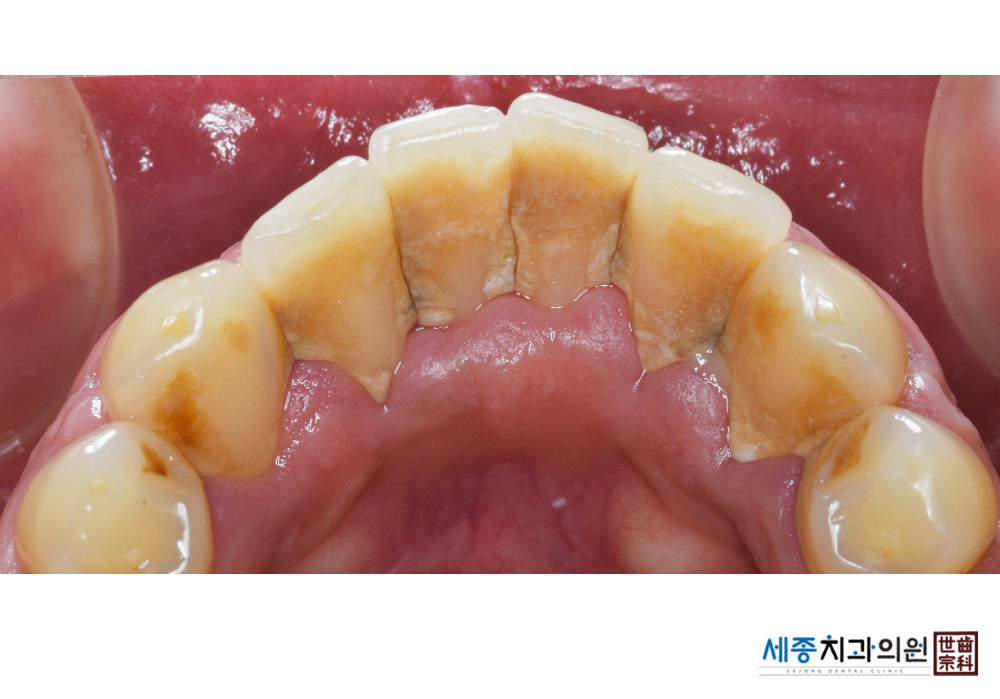

[스케일링] 치주질환 예방 스케일링 치료

치료전 : 2019-03-06

치료후 : 2019-03-06

가글마취&저주파 스켈러를 사용한 스케일링